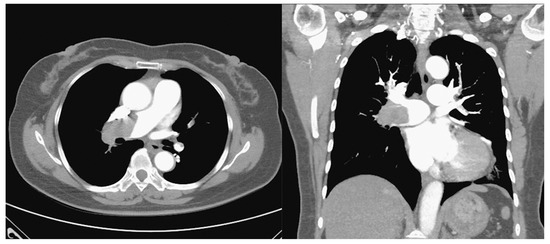

Pulmonary Embolism and Severe Asthma: Case Report and Literature Review

2. Case Presentation